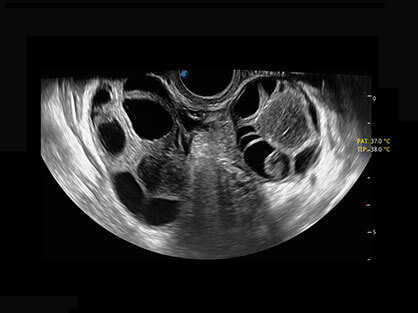

宽频带腹部凸阵探头和腹部容积探头、大角度腔内探头和腔内容积探头、独特的生殖专用曲柄探头,为妇产应用提供全面诊疗方案。

大角度腔内容积探头,可完整包络子宫及盆底结构,充分展示组织结构毗邻关系。